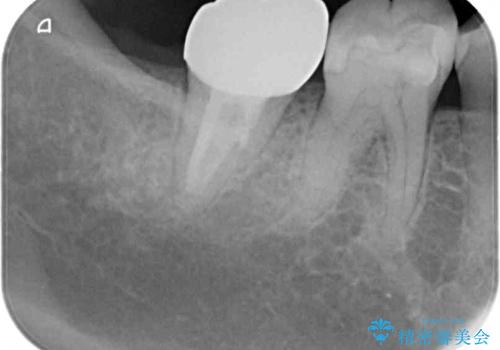

前方に傾斜したまま補綴治療を行うと、歯間にものが挟まりやすい上に、歯間ブラシなどの清掃器具も通しにくくなるため、清掃性が著しく低下します。

多少治療期間はかかりますが、部分矯正による歯の移動は非常に有意義な治療手段です。